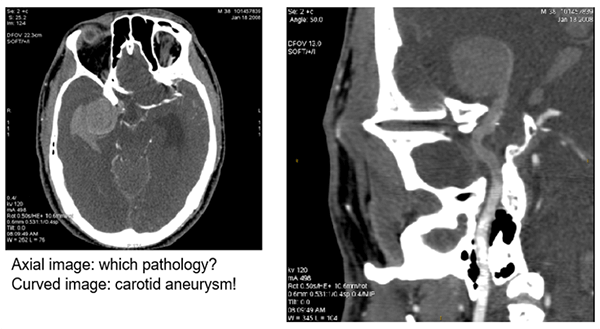

Aneurysm

The image post-processed with a curved technique shows a carotid aneurysm in the upper third of the image on the right.